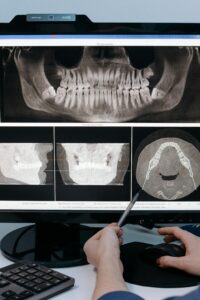

Tooth Replacement Options After Loss

After a tooth is lost, common replacements include a dental implant and crown, a fixed bridge that uses neighboring teeth for support, a removable partial denture, or a full denture when many teeth are missing. The right choice depends on your goals, oral health, bone support, and the location of the gap.

A back molar is extracted after a deep crack. An implant replaces the root and holds a crown; this avoids shaping the adjacent teeth and helps preserve biting support. For full arches, implant overdentures can add stability compared with traditional dentures. Selection also depends on your health, bone quality, and the tooth loss causes involved. Planning the number and position of implants, as well as how your bite loads them, influences long‑term success [9].

Fixed bridges fill a single‑tooth space by crowning the teeth on either side and suspending a false tooth between them. This can be a good option when those neighbors already need crowns, or when implant placement is not advisable. Removable partial dentures use clasps and a base to replace several missing teeth and are often a lower‑invasiveness solution, though they require daily removal and cleaning. If you are weighing a single‑tooth gap, this comparison can help you compare bridges and implants. When a compromised tooth can be treated predictably, preserving it may be cost‑effective compared with extraction and implant placement in some severe periodontal cases [10].

Timing matters too. In certain cases, early replacement helps maintain gum shape and function; in others, short healing periods or bone grafting are recommended first. Any option benefits from steady home care and regular checks to protect the surrounding teeth and gums. If you are unsure where to start, a focused exam and bite assessment will clarify which path best supports chewing, speech, and long‑term comfort. Thoughtful planning helps you chew comfortably and smile with confidence.